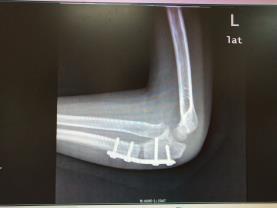

肱骨外髁陈旧性骨折